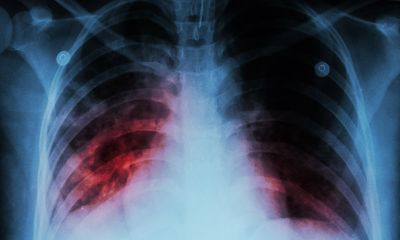

Над 4 хил. годишно се разболяват от рак на белия дроб у нас - над 3 хил. от тях са мъже

Всяка година в страната ни се диагностицират 4250 нови случая на рак на белия дроб, като 3260 са сред мъже. Това каза пред журналисти проф. Асен Дудов, председател на Българското онкологично дружество, цитиран от БТА. По думите му тази локализация е водеща причина за смърт от онкологично заболяване в България. Причини за повишаване на случаите на рак на белия дроб са тютюнопушене, излагане на азбест, пасивно пушене, генетични предпоставки и други.

Повечето случаи на болестта се диагностицират късно - в трети или четвърти стадий, което възпрепятства възможностите за лечение. Късната диагноза е причината за високата смъртност, като 80 на сто от пациентите загиват в рамките на 1 година след диагностицирането.

Целите, които биха могли да ускорят диагностиката и лечението, са повишаване на информираността на населението, намаляване на времето между консултациите и началото на лечението, както и усъвършенстване на програмите за скрининг сред рисковите групи.